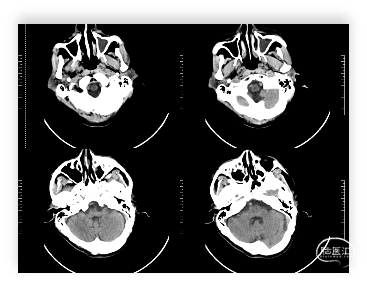

头颅CT:双侧基底节及双侧额叶多发腔隙性脑梗塞;左侧上颌窦炎。

入院时头颅CT